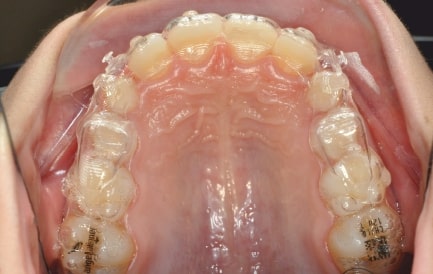

Malocclusion A6 Correction of Mandibular Retrusion in Growth phase patient | Skeletal Class II | Class II Division 1 malocclusion | Deep bite | Mixed dentition

Initial Photos and datas

Clinical examination and diagnosis

• Upper diastema (11-21)

• Reduced Transversal Diameters

• Upper Archform enlargement (dental expansion)